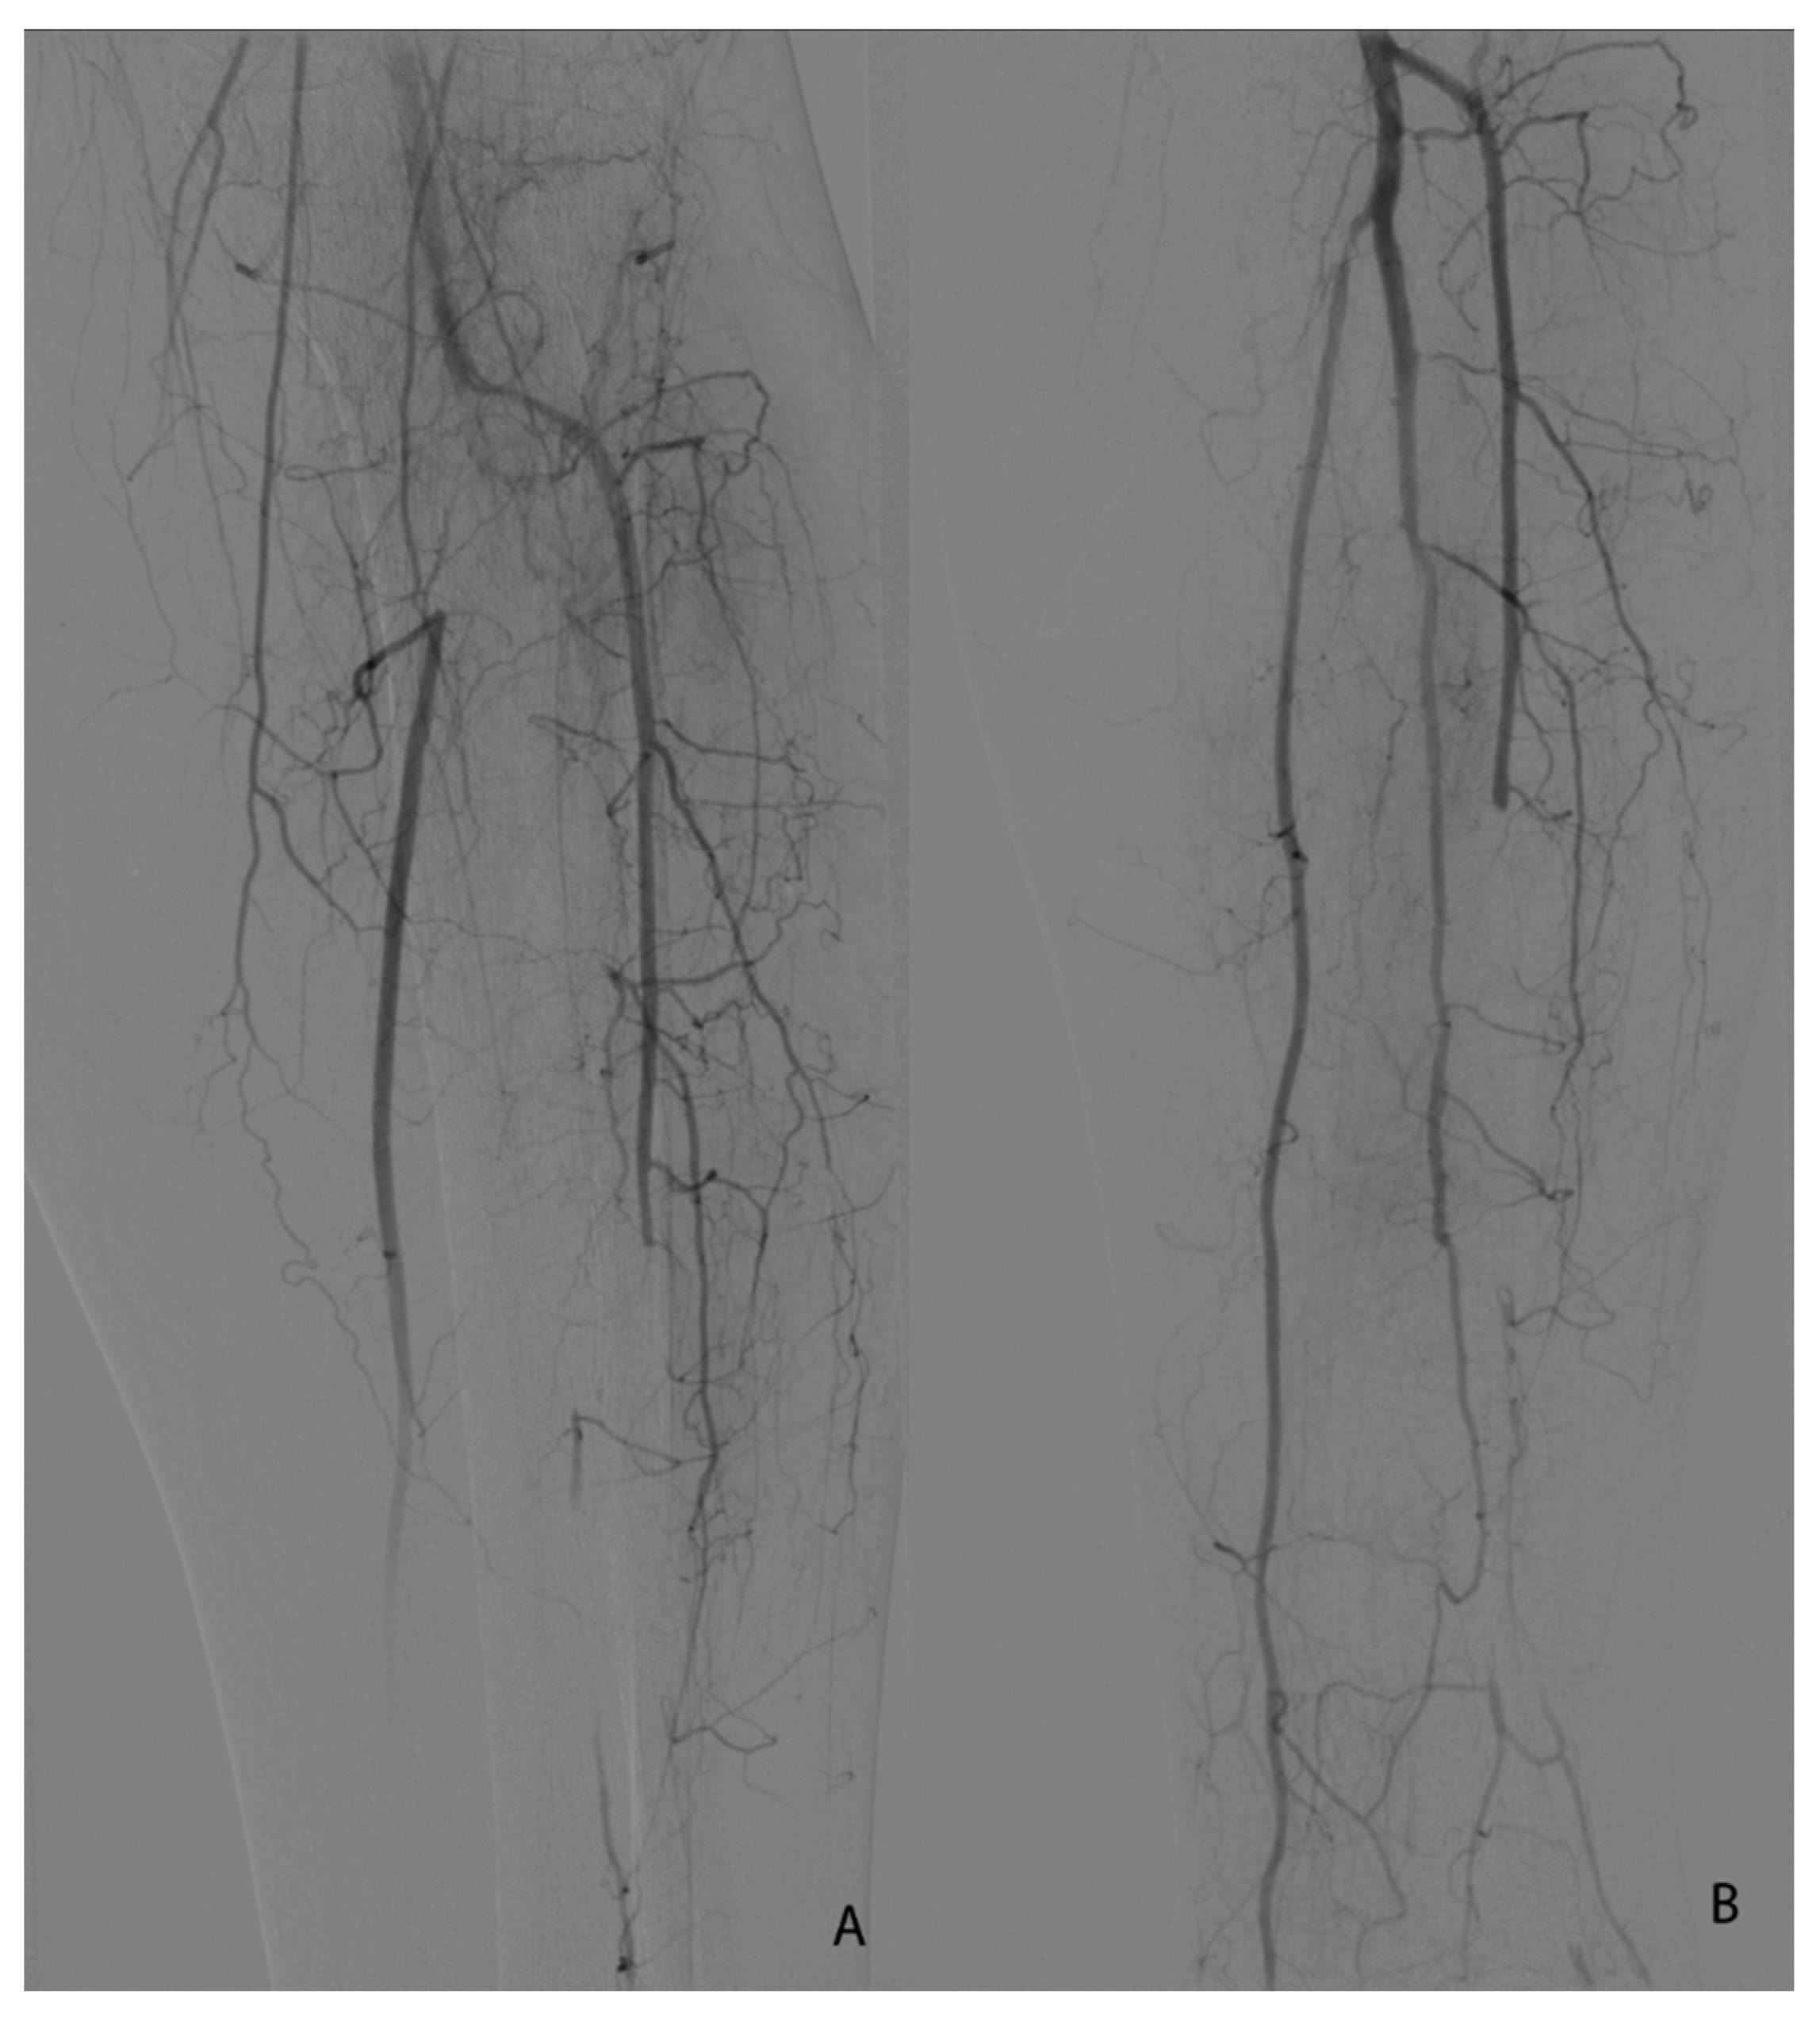

Figure 4.

(A,B). Seldinger angiography of a 64 yo patient with stage IIB Rutherford acute lower left limb ischemia 2 days after SARS-CoV-2 diagnosis. (A)—initial image before thrombolysis initiation. (B)—final image after balloon angioplasty of the initial segment of the posterior tibial artery.

For the endovascular approach (four patients—18.18%), the access was either femoral (three patients—13.63%) or brachial (one patient—4.54%). After 24 h, we performed control angiography after thrombolysis and additional procedures were needed: superficial femoral plain balloon angioplasty (two patients—9.09%) and one at the level of the initial segment of the posterior tibial artery (one patient 4.54%).